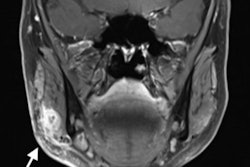

After a thorough exam and a flexible fiber-optic nasopharyngolaryngoscopy didn't reveal the foreign body in her upper aerodigestive tract, the clinicians saw a tender, nonfluctuant, diffuse swelling of about 2 x 2 cm on the left side of her neck. The x-ray showed a long, thin, smooth, and impinged foreign body, lying lateral to the esophagus. CT showed that something metallic and 3 cm in length had pierced through the woman's left internal jugular vein and the left sternocleidomastoid muscle. Doctors used 3D reconstruction and virtual endoscopy images to localize the needle and plan for the surgery, the authors wrote.

A: An x-ray showed a long, thin, and impinged foreign body. B: CT confirmed that the body was metallic and 3 cm in length. C: 3D reconstructed images were used for planning the removal of the needle. All images courtesy of Dr. Hassen Mohammed et al. Licensed under CC BY-NC 4.0.Rare but not impossible